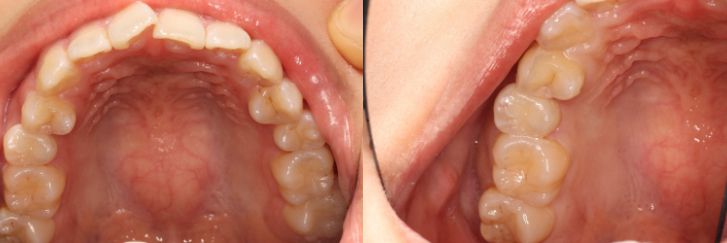

インレーの症例

インレーをやりかえ

患者情報

24歳 女性

主訴

詰め物をやりかえたい

治療内容

詰め物のやりかえ

治療期間

2週間

治療におけるリスク

処置後しみる事がある

費用

8万円

※ クリックして拡大することができます。